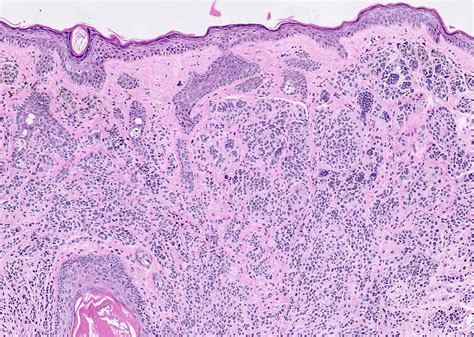

An Intradermal Pigmented Nevus is a type of mole that develops within the dermis, the layer of skin beneath the epidermis. Unlike other types of moles, which can be raised or flat, intradermal nevi are typically raised and have a smooth, dome-shaped appearance. They are often flesh-colored or slightly darker and can appear anywhere on the body. These nevi are usually present at birth or develop during childhood and adolescence.

• Dermoscopy: This non-invasive technique uses a specialized microscope to examine the mole more closely. It can help differentiate between benign and malignant lesions.

• Biopsy: In some cases, a biopsy may be performed to confirm the diagnosis. This involves removing a small sample of the mole for laboratory analysis.

It is important to note that while most intradermal nevi are benign, any suspicious changes should be promptly evaluated to rule out skin cancer.